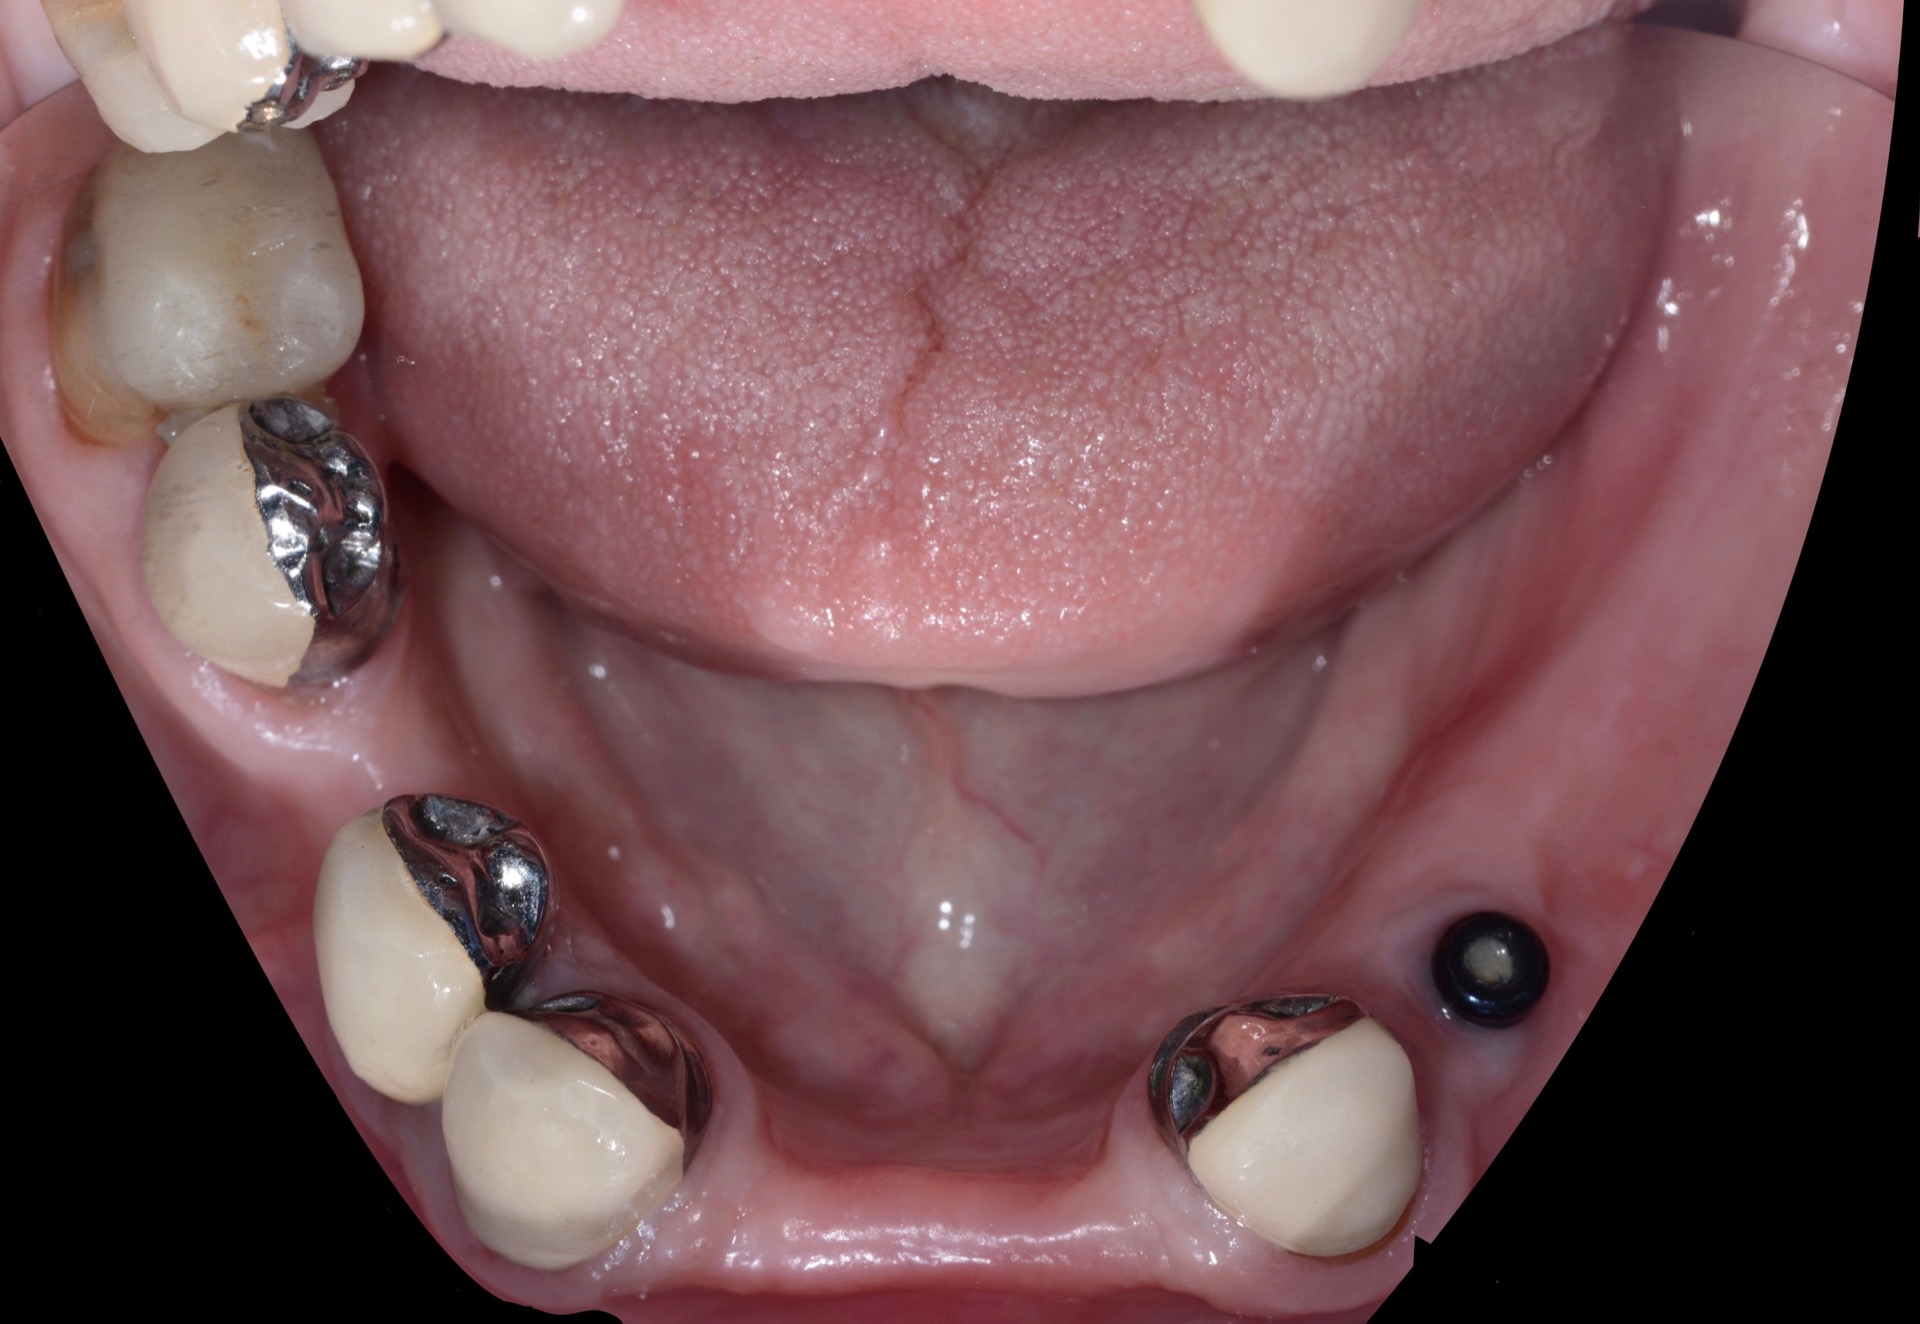

Στην κάτω γνάθο, τα υπάρχοντα δόντια δέχτηκαν στεφάνες, ενώ παράλληλα, τοποθετήθηκε ένα εμφύτευμα για την βελτίωση της συγκράτησης της νέας μερικής οδοντοστοιχίας που κατασκευάστηκε.